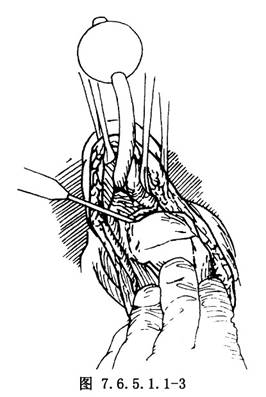

3.緊貼兩遠側縫線下方,用電刀橫向切開膀胱頸前壁全層,明確膀胱三角區和輸尿管開口位置後,繼續於膀胱內用電刀向兩側延長。男性應切至露出精囊及輸精管,使膀胱底部可充分上移約2.5cm(圖7.6.5.1.1-3)。